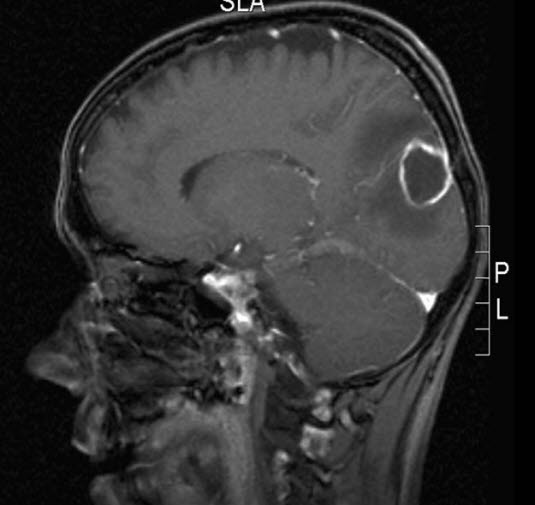

Hjerneabscess, sagittalt snitt

Gjengitt med tillatelse av Radiologisk avdeling, Universitetssykehuset Nord-Norge